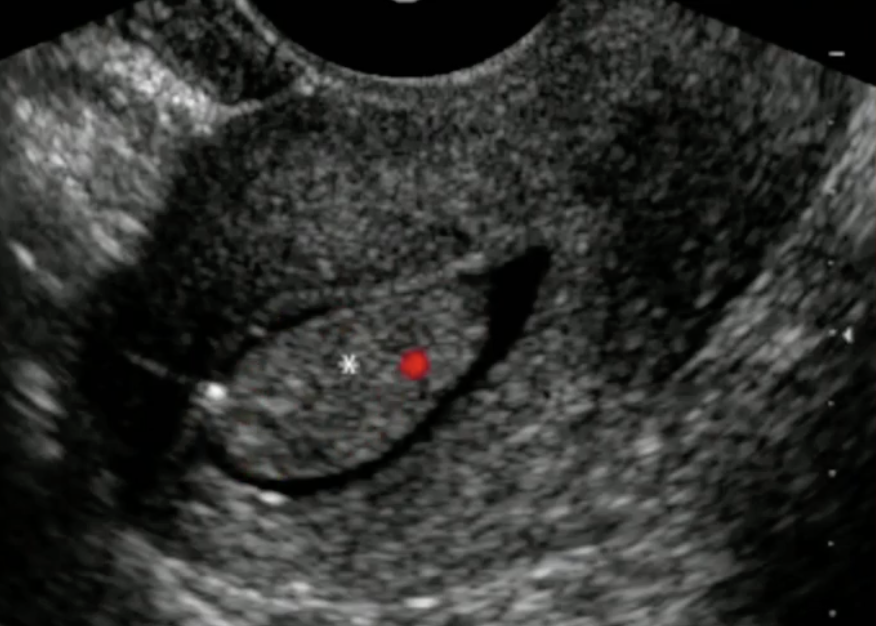

Qual o diagnóstico da paciente?

A

Incontinência Urinária de Esforço por Hipermobilidade Cervical

Curiosidade: Tratamento inicial é MEV